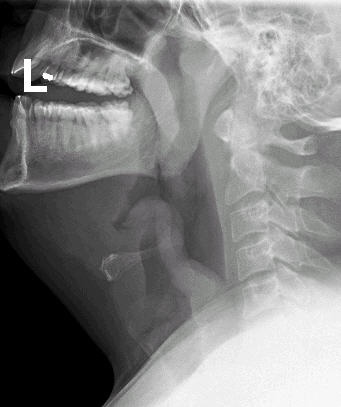

A visualização direta da epiglote (sob circunstâncias controladas na sala de cirurgia, com capacidade imediata de intubação em caso de fechamento das vias aéreas) ou radiografia lateral do pescoço.[Figure caption and citation for the preceding image starts]: Filme lateral do pescoço demonstrando epiglotiteDo acervo pessoal de Dr. Petri; uso autorizado [Citation ends].